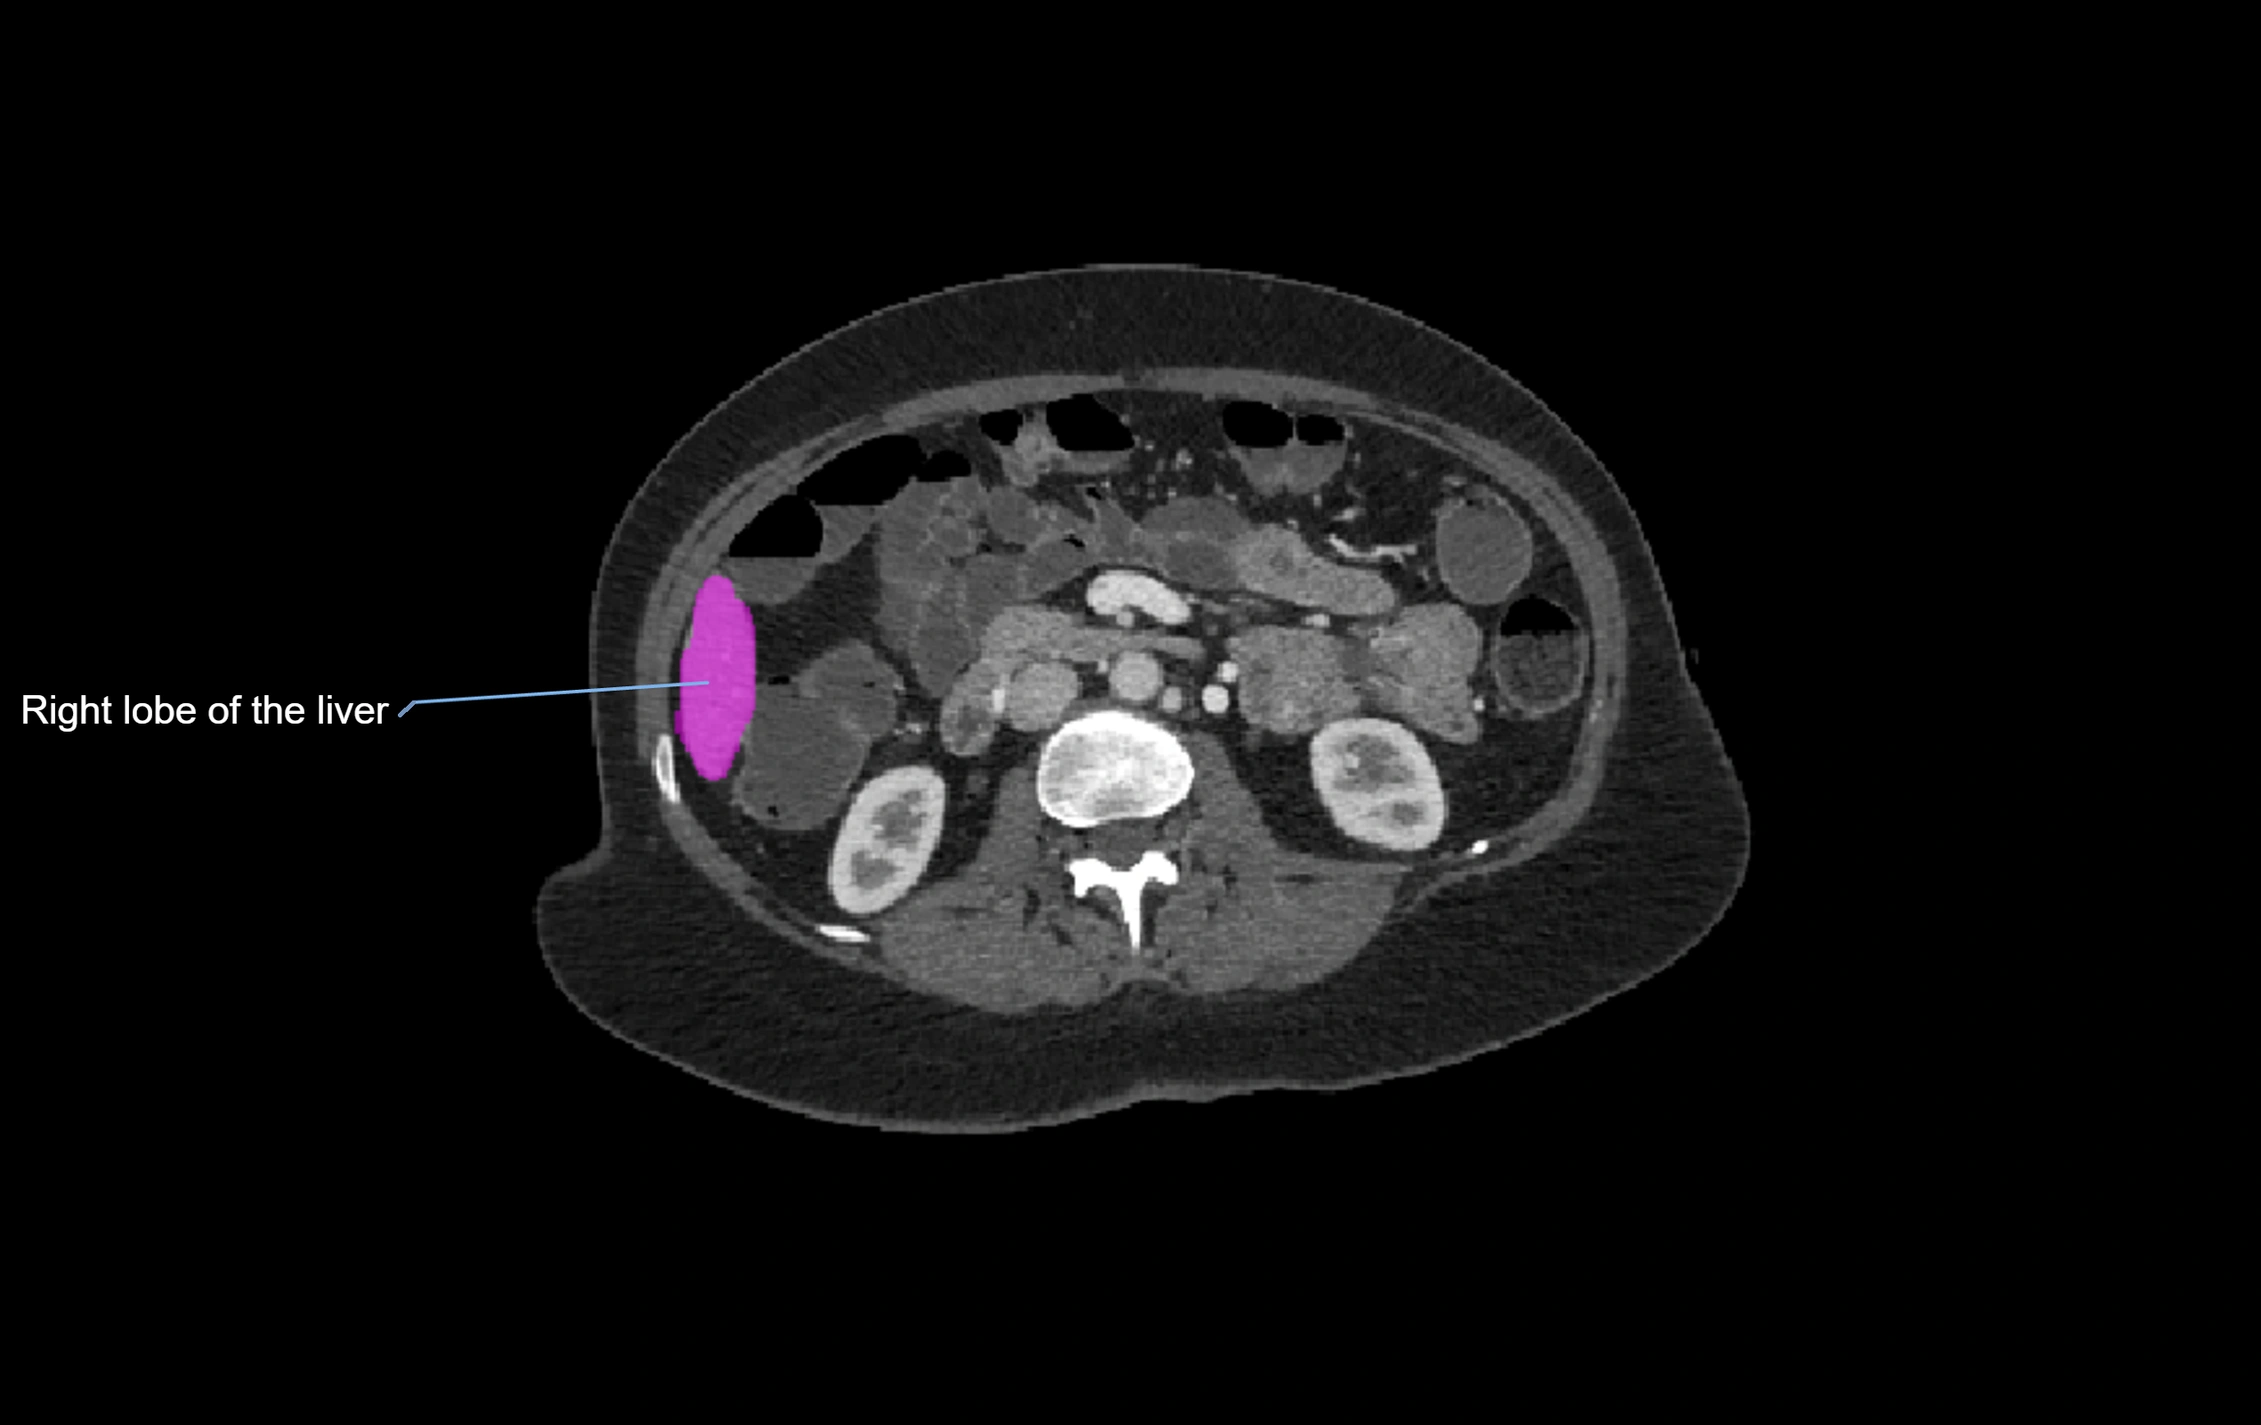

CT Appearance

CT Pre-Contrast:

• Caudate lobe appears as a soft-tissue density, isodense to the rest of the liver

• Enlargement may be appreciated in cirrhosis or Budd–Chiari syndrome

CT Image

image